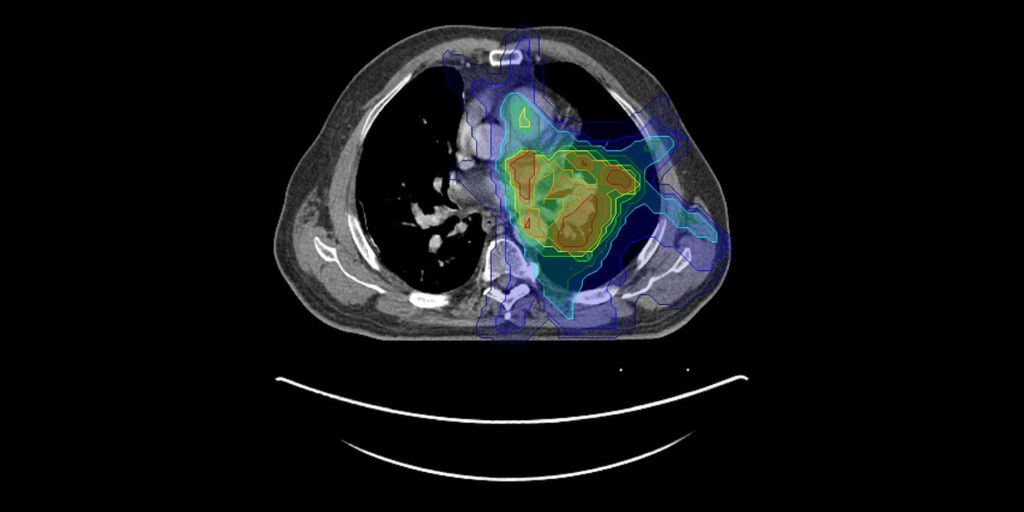

AI for Radiation Oncology

AI-based updating of radiation treatment plans and AI-based contouring of tumors and organs for improved radiotherapy.

Read more →